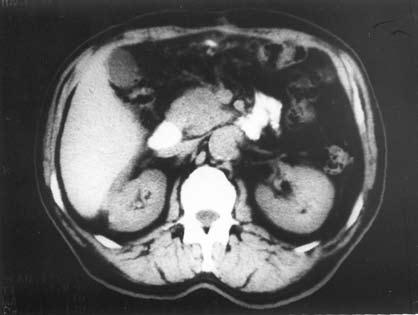

Компьютерная томография (КТ) является рентгенологическим методом высокой разрешающей способности, достаточно широко используемым при исследовании ПЖ. В принципе метод позволяет получить данные, аналогичные УЗИ, однако в ряде случаев дает возможность уточнить последние, например, при ожирении больного, наличии метеоризма, преимущественной локализации изменений в области хвоста железы (рис. 140).

Вместе с тем встречаются случаи, когда очаговые изменения, выявленные при УЗИ, не обнаруживаются при КТ (изоденсны), или наоборот и, таким образом, оба исследования дополняют друг друга. Учитывая высокую стоимость КТ, ее применение следует считать необходимым в случаях, когда на основании УЗИ не удается создать достаточно четкое представление о патологических изменениях в ПЖ (образование изоэхогенно частично).

В норме поджелудочная железа определяется на компьютерных томограммах в виде относительно гомогенного образования S‑образной формы. Признаками поражения железы являются неоднородность ее тени с участками уплотнения и разряжения, расширения, сужения и деформации протоков, одиночные или множественные полостные жидкостные образования. Для ложной кисты, как и при УЗИ, характерно наличие капсулы и однородное или неоднородное (при наличии в полости секвестров или замазкообразного детрита) содержимое. Высока разрешающая способность КТ при наличии в железе обызвествлений и протоковых конкрементов. Злокачественные новообразования выглядят при КТ очагами, плотность которых ниже плотности железы.

Рис. 140. КТ при хроническом кальцифицирующем панкреатите. На снимке видны кисты головки ПЖ, расширенный ГПП и кальцинат в его просвете.